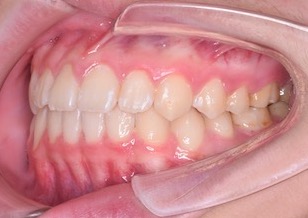

混合歯列期で、萌え代わりの完了している上下顎前歯部の永久歯に叢生(ガタガタの歯並び)を認めます。右側の側方歯は交叉咬合となっています。

パノラマレントゲン所見において、上顎歯列の(萌え代わりが完了していない)永久側方歯部にもスペース不足によるあきらかな叢生の症状が認められます。